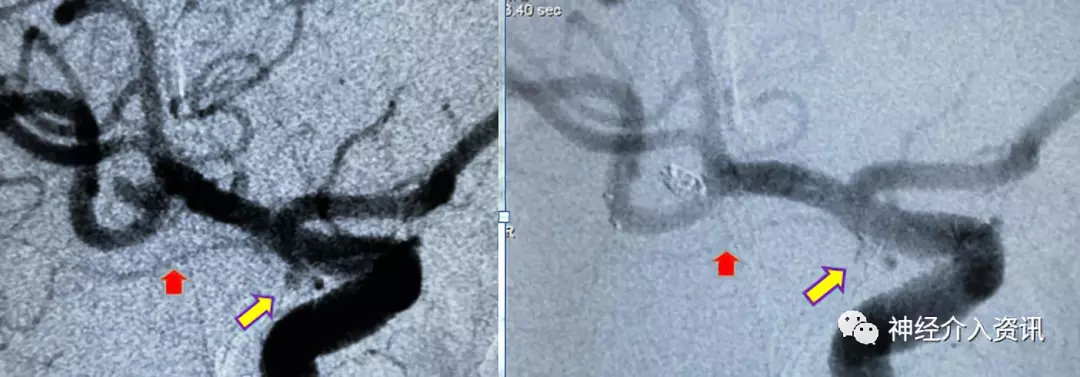

先处理大脑中动脉分叉部动脉瘤,应用Echelon-10微导管在微导丝导引下置于动脉瘤的中心,将支架导管置入同侧大脑中动脉M2中,释放4*15mm Solitaire™ AB支架一枚,跨越动脉瘤颈,应用Axium™ Prime ES 1.5mm*3cm弹簧圈及1mm*3cm弹簧圈将大脑中动脉动脉瘤致密填塞,在栓塞过程中微导管始终保持稳定,弹簧圈顺利推送无顶管现象,完成对该动脉瘤的栓塞;继续处理右脉络膜前动脉动脉瘤, Echelon 10在微导丝导引下置于动脉瘤的中心,释放3.5*15mm支架一枚,跨越动脉瘤颈,应用一枚Axium™ Prime ES 1mm*3cm弹簧圈将动脉瘤致密填塞,完成对两个动脉瘤的栓塞。

图三 大脑中动脉瘤致密栓塞